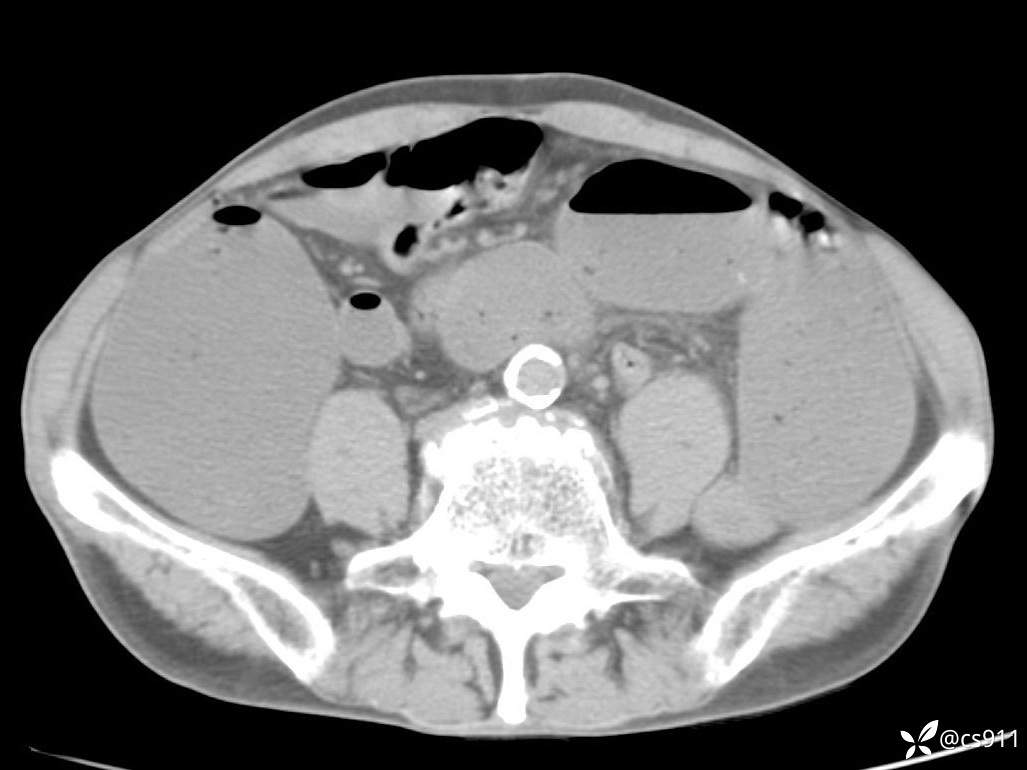

急腹症之急诊CT,原因?答案公布

男,77岁,腹痛、腹胀伴恶心呕吐1天。呕吐胃内容物,非喷射性呕吐,有咖啡色样胃内容物,诉有胃穿孔病史。查体:全腹平,下腹部压痛,全腹无反跳痛,叩诊呈浊音,移动性浊音阴性,肠鸣音减弱,1-2次/分。肛检:直肠未扪及明显肿物,可触及大量粪块。

T 36.6℃ P 80次/分 R 26次/分 BP 100/60mmHg

白细胞(WBC) H 14.55 10e9/L 4-10

中性粒细胞百分率(NEUT%) H 85.7 % 40-75

血淀粉酶(AMY) HH 1859 U/L 35-135

癌胚抗原(CEA) H 27.44 ng/ml 0-5

呕吐物 潜血试验 * 阳性 阴性

患者轮椅入室检查神志清楚, 能配合摆位和呼吸